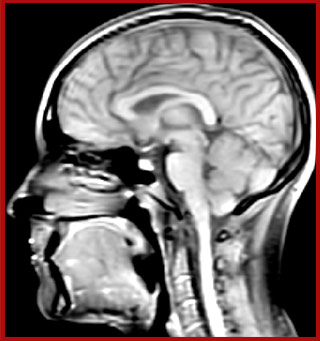

T1 - weighted

Myelin water imaging - T1 weighted

Myelin water imaging (echo 1)

Myelin water imaging with SENSE

Myelin water imaging with Compressed SENSE

With SENSE

With Compressed SENSE

Acquired resolution:

1 x 2 x 5 mm3

1.5 x 2 x 3 mm3

Number of echoes:

32 or 48

56

Echo spacing:

10 ms or 8 ms

7 ms

T1 - Weighted, Myelin Water Fraction Superimposed

MWI Spinal cord coverage

Spinal cord coverage

MWI Smaller, more isotropic voxels

Smaller, more isotropic voxels

MWI Excellent detail in quantitative maps

Excellent detail in quantitative maps

Images courtesy of Adam Dvorak, Department of Physics and Astronomy, University of British Columbia

20%

Myelin water fraction

0%